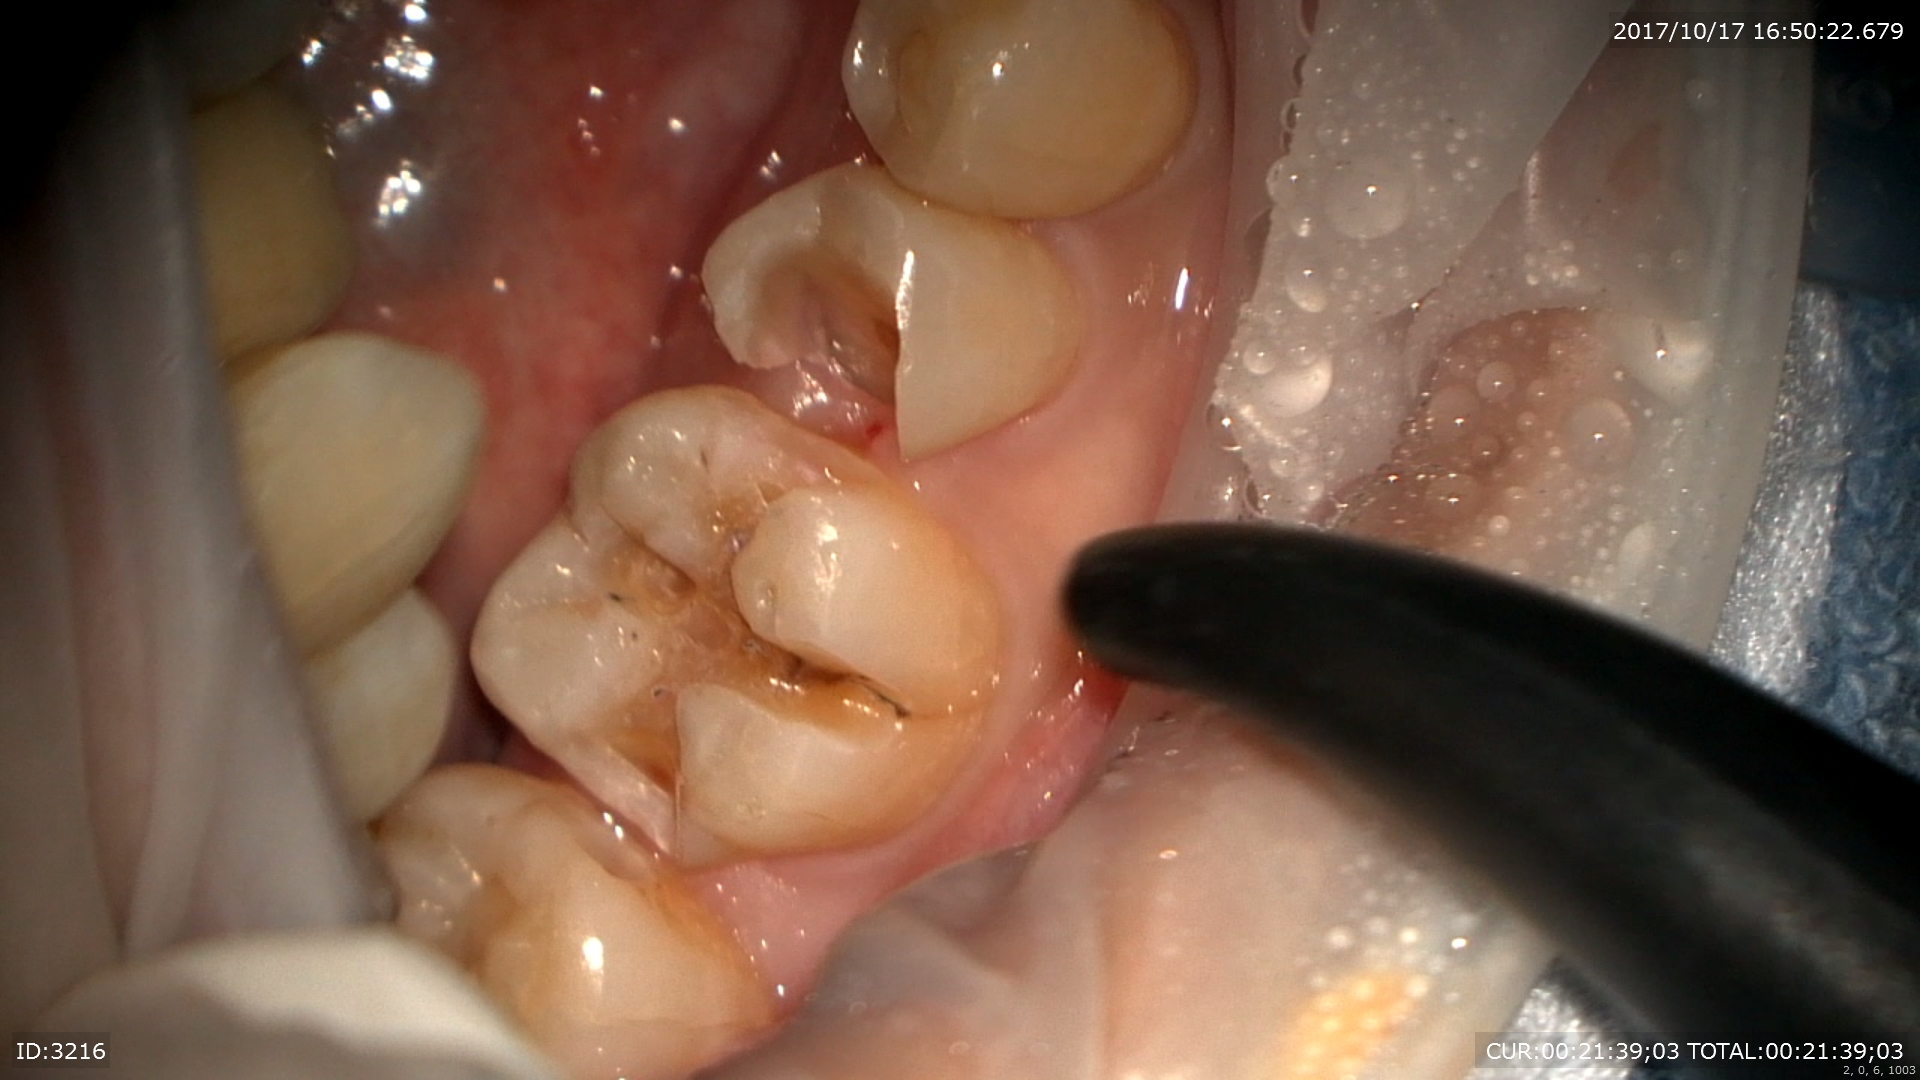

むし歯が取りきれました。直ぐ神経です!!守らなきゃ

神経保護を行いました。